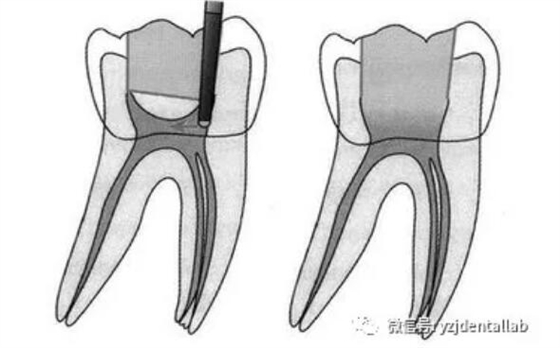

二、開髓去腐質(zhì)

去凈腐質(zhì)和原有充填物、揭凈隨頂,看到整個(gè)髓底解剖結(jié)構(gòu)、髓壁與根管壁連續(xù)流暢、沒有牙頸部臺(tái)階,沒有過度切割髓壁和髓底以便后續(xù)治療順利進(jìn)行。

開髓步驟:

局麻--上橡皮障--去除所有腐質(zhì)--接髓頂--形成與根尖孔1/3的直線。

七、根管充填

充填時(shí)機(jī),無自覺癥狀,無明顯叩疼,根管內(nèi)無異味,無滲出,無急性尖周炎癥狀即可充填,不必等到所有癥狀消失,反復(fù)的封藥容易對(duì)尖周造成大大刺激。

充填的質(zhì)控標(biāo)準(zhǔn):

a、充填物距根尖小于等于2mm;

b、充填致密,連續(xù),錐度合適;

c、充填完畢燙牙膠尖根管口下2~3mm,小號(hào)充填器冷加壓;